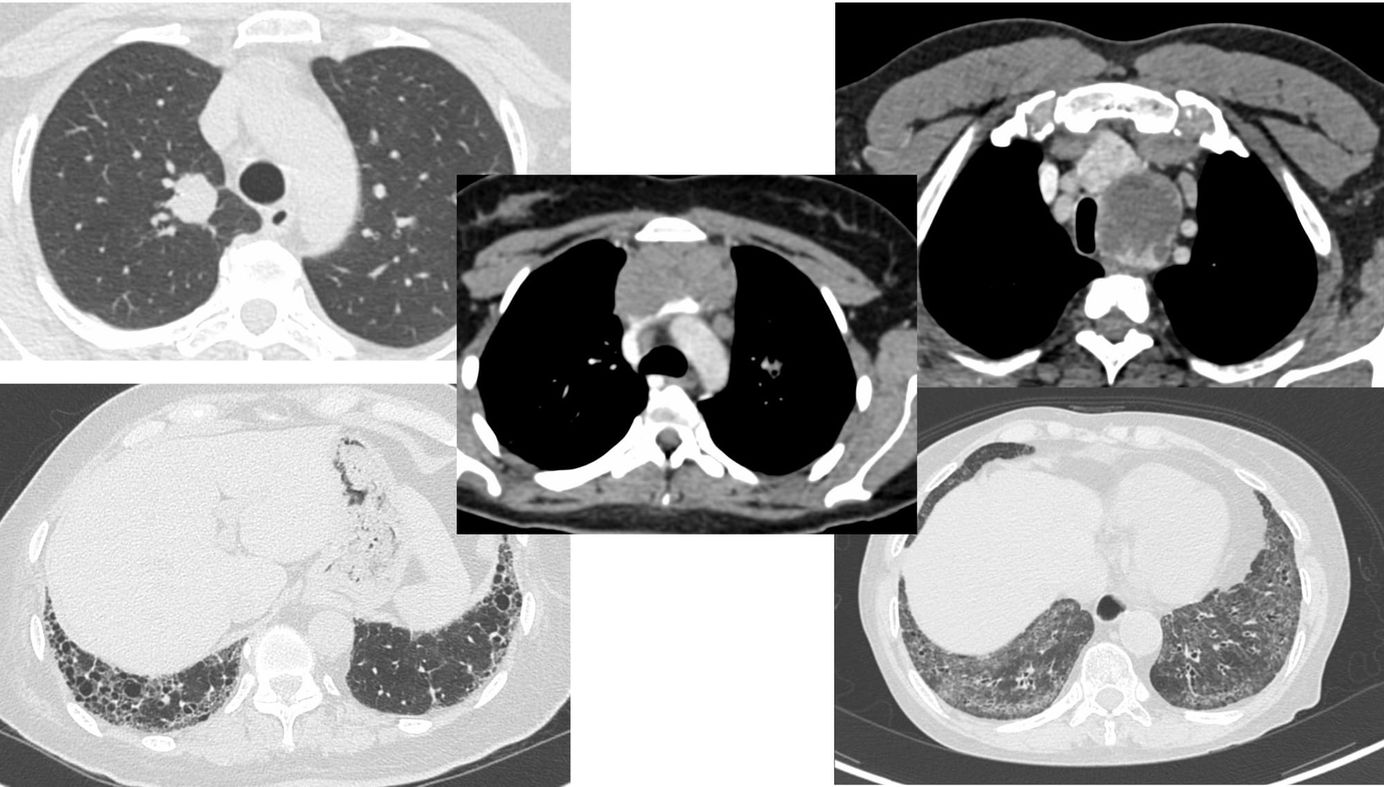

CT Chest Cases of Feb 2026 - Five Cases Discussed Using the Osirix Viewer - No Powerpoint Members Public

5 cases discussed using Osirix - no Powerpoint.